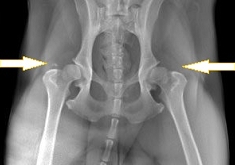

犬の股関節 (レントゲン画像)

正常な股関節

左右対称で

寛骨臼内に大腿骨頭が正しく収まっている

股関節形成不全症

寛骨臼が不完全で

大腿骨頭が収まっていない

片方は寛骨臼が無く

大腿骨頭が飛びだしている